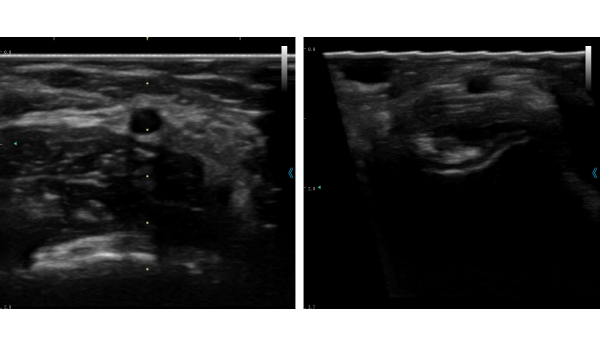

iSoniQ80系列

可视化随身诊疗彩超

普博新一代掌上超声系统,提供多探头解决方案,采用先进的芯片及图像处理技术,呈现出清晰的图像,可应对各种复杂的临床应用场景;既是临床视诊器,也是基层随身超。

二代芯片

升级后,单颗集成32物理通道,低功耗图像更优质

多种图像优化技术,提升二维图像分辨力及血流灵敏度

专业算法,增强图像细节,提高图像清晰度

特色应用

声速偏转,增强穿刺显影

智能预设,一键呈现最佳的参数模式

甲乳、肾内、肿瘤等,POC科室专业化穿刺解决方案